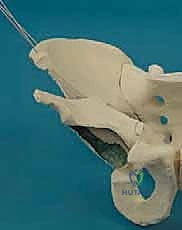

The Five Interconnected Osteotomies

The hallmark of the Bernese PAO is the sequence of five precise osteotomies.

1. The Anterior Ischial Osteotomy: This is arguably the most technically demanding cut. Working through the interval medial to the psoas tendon, a specialized angled osteotome is guided down the quadrilateral plate to the infracotyloid groove. The cut is made approximately 1.5 cm distal to the acetabular articular surface, directed posteriorly and slightly laterally, intentionally stopping short of complete cortical disruption to protect the sciatic nerve posteriorly and the MFCA laterally.

2. The Superior Pubic Ramus Osteotomy: A blunt retractor protects the obturator nerve and vessels. Using an oscillating saw or osteotome, the superior pubic ramus is cut obliquely, just medial to the iliopectineal eminence. This cut must be complete to allow for fragment mobilization.

- The Supra-acetabular Iliac Osteotomy: Using an oscillating saw, a transverse cut is made across the ilium, originating just inferior to the ASIS and terminating 1 to 2 cm short of the pelvic brim, directing the cut toward the apex of the greater sciatic notch.

- The Posterior Column (Retroacetabular) Osteotomy: This cut connects the medial aspect of the supra-acetabular cut to the posterior aspect of the ischial cut. Using a long, straight osteotome driven down the quadrilateral plate, the cut is angled approximately 120 degrees from the iliac cut, passing completely within the posterior column, remaining extra-articular, and crucially leaving the posterior cortex of the posterior column intact for pelvic stability.

- The Final Liberation: A specialized bone hook or a heavy Schanz pin is placed into the supra-acetabular region of the fragment. With controlled, deliberate force, the remaining intact bone bridges (specifically the posterior ischial cortex) are fractured, fully mobilizing the acetabular fragment.